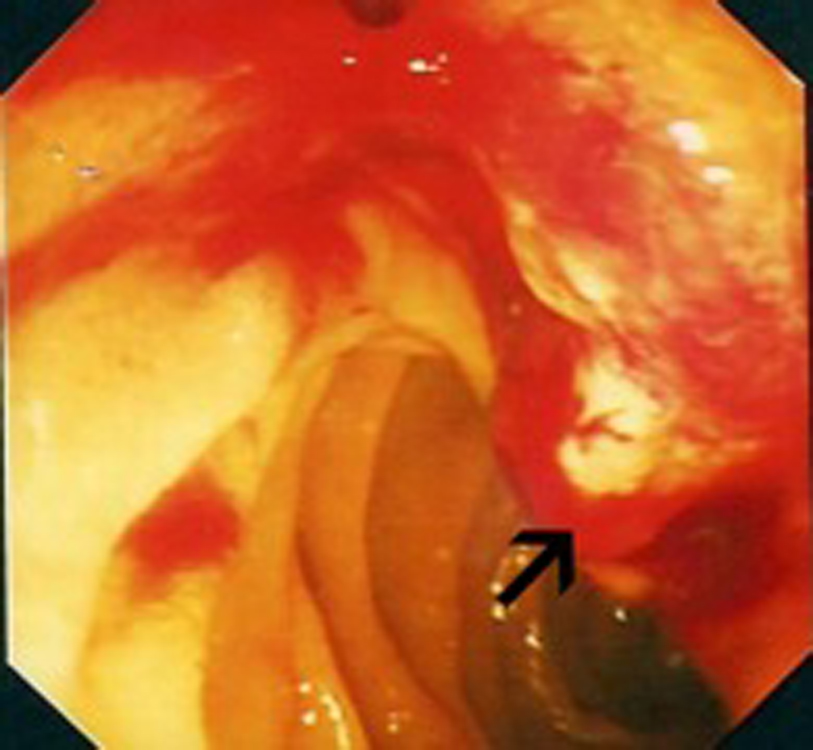

In July 2009, she presented to the Oncology Day Unit with one week history of obstructive jaundice and a two-day history of right upper quadrant colicky pain. Liver function tests were grossly abnormal with a cholestatic picture, (Alk Phos 750 IU/L, ALT 598 IU/L, γGT 1246 IU/L, bilirubin 228 µmol/L). Initial ultrasonographic assessment proved difficult because of her body habitus, but did suggest ductal dilatation with two areas of low density in the left lobe of the liver. Further imaging in the form of magnetic resonance cholangiopancreaticogram (MRCP) showed high grade intrahepatic bile duct dilatation with a dilated common bile duct to its mid portion, while the pancreatic duct was of normal calibre. There was a suggestion of stricture at the distal end of the common bile duct. Endoscopic examination revealed a swollen ampulla (Fig. 1), and histopathological examination showed fragments of ulcerated small intestinal mucosa extensively infiltrated by poorly differentiated carcinoma with focal clear cell morphology noted. The tumor cells stained positive for pancytokeratin AE1/AE3, vimentin, EMA and CD10 while negative for CK7, CK20 and CDX2. RCC was non-contributory due to excess background staining. The above immunohistochemical findings are most consistent with a metastasis from this lady’s known renal cell carcinoma.

![]() Click for large image | Figure 1. Endoscopic view: black arrow pointing to bleeding mass at the ampulla of Vater. |